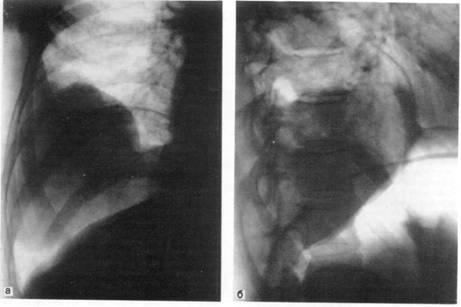

Показанием к введению воздуха или кислорода в брюшную полость с последующим рентгенологическим обследованием являются образования, прилежащие к нижним долям легких и куполу диафрагмы, когда не удается ответить на вопрос: располагаются ли они в легком, исходят из диафрагмы или находятся в поддиафрагмальном пространстве, например в печени (рис. 4).

Рис. 4. Доброкачественная опухоль правого легкого в условиях искусственного пневмоперитонеума.

а — прямая рентгенограмма; б — боковая рентгенограмма.